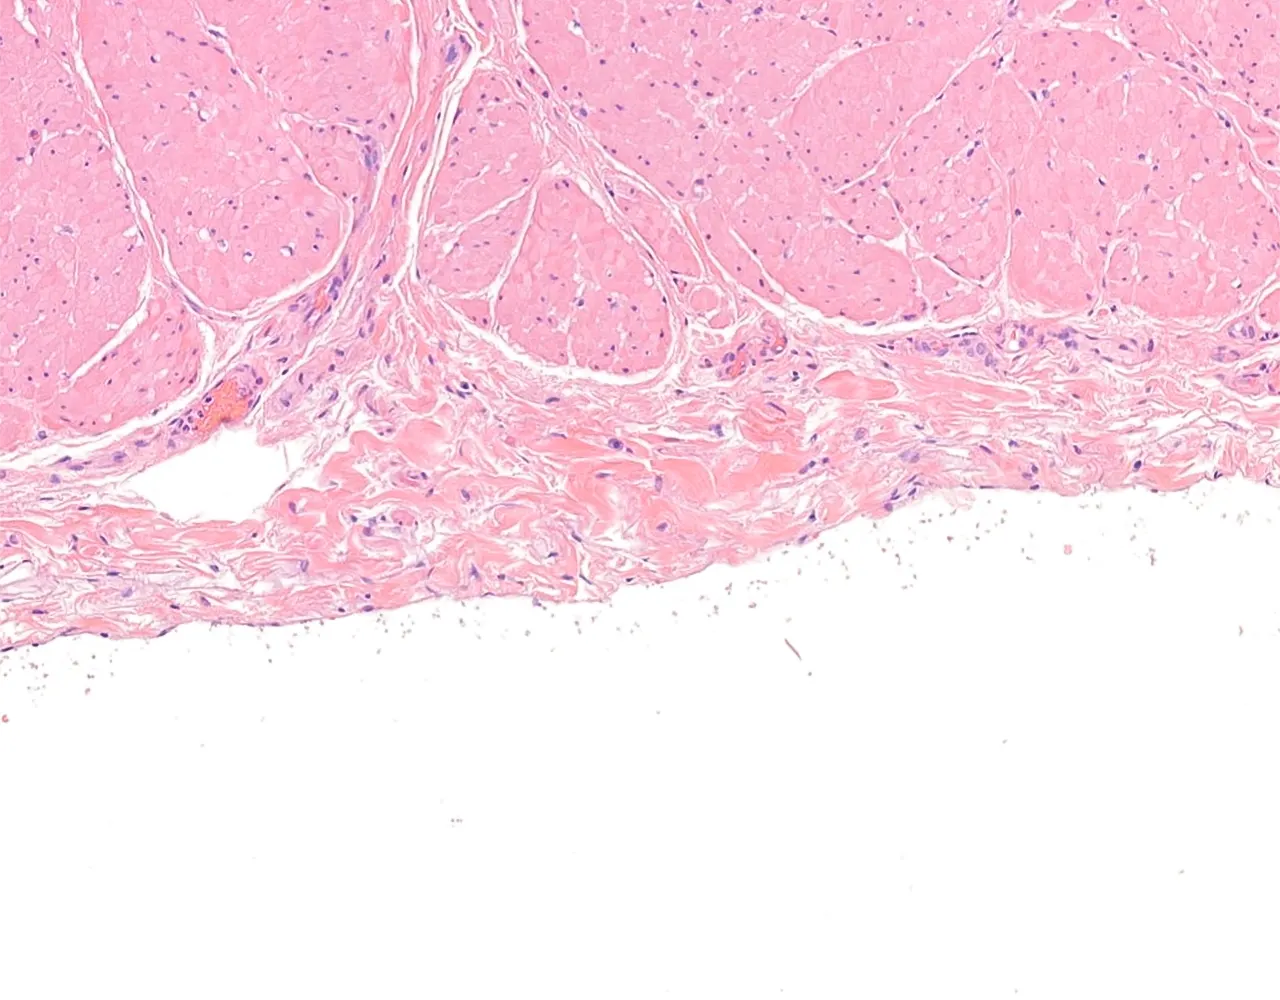

- Le côlon ascendant et le côlon descendant sont majoritairement rétropéritonéaux, alors que le côlon transverse et le côlon sigmoïde sont intrapéritonéaux et recouverts par la séreuse.

- Le rectum est partiellement recouvert par une séreuse dans sa portion proximale, le reste du rectum est entouré par une adventice.